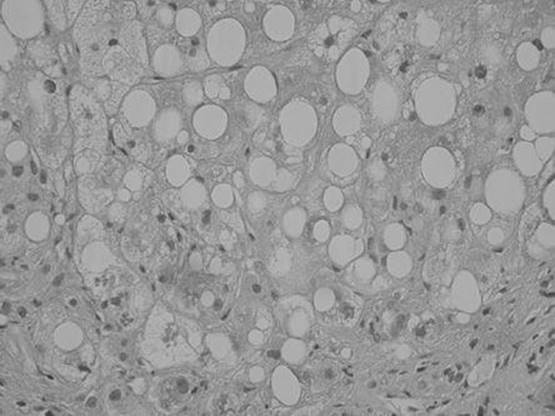

A 46-year-old man who admits to drinking “3 or 4 beers a day” presents with jaundice, right upper quadrant abdominal pain, and fever. A liver biopsy was eventually performed and is shown below. What is the most likely diagnosis?

Figure 51-2

Alcoholic hepatitis. Typical features of alcoholic hepatitis include Mallory’s hyaline, which is an eosinophilic inclusion within hepatocytes that stains with ubiquitin, neutrophils surrounding individual degenerating hepatocytes, sclerosing hyaline necrosis, and steatosis, predominantly macrovesicular.